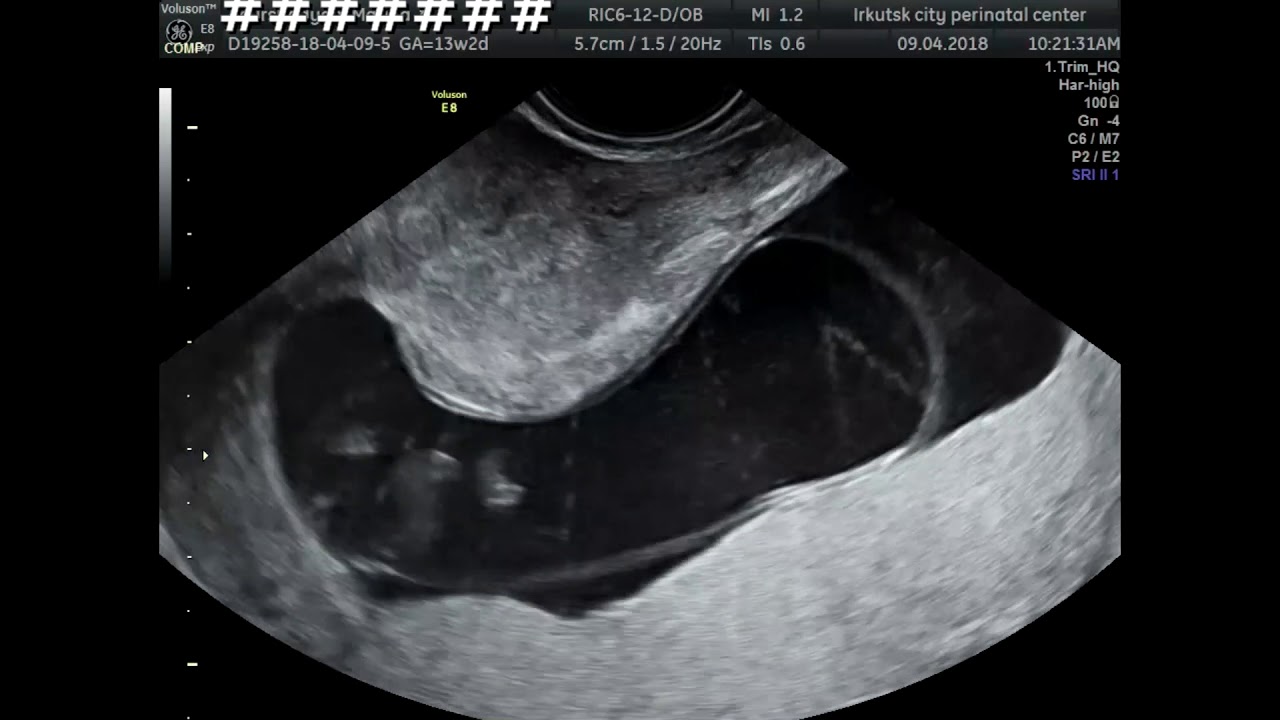

Диагностирование акрании производится при помощи проведения ультразвукового исследования, когда основные костные ткани уже сформированы.

Выявление акрании происходит во время первого скрининга, который приблизительно проводиться с 10 по 13 неделю беременности.

Нарушения отлично видны на первом плановом УЗИ, поэтому тратить время на подтверждение диагноза не придется.

Если при диагностическом УЗИ специалист отчетливо различает мозговую ткань, а основные костные ткани еще не сформированы – диагноз акрания неизбежен. В этом случае женщине рекомендуется провести аборт до 12-й недели беременности.

Как правило, анэнцефалия обнаруживается при ультразвуковом исследовании (эхограмма анэнцефалии) во время беременности на сроке с 11-12 недель, также характерно повышение в крови беременной уровня альфа-фетопротеина с 13-14 недель беременности. Тесты на наличие у ребенка анэнцефалии могут быть проведены женщине уже на ранних сроках беременности, если кому-либо из членов семьи уже пришлось ранее столкнуться с данным заболеванием.

- УЗИ. Высокочастотные звуковые волны могут создавать изображения (сонограммы) развивающегося плода на экране компьютера. Сонограмма может показать физические признаки анэнцефалии.